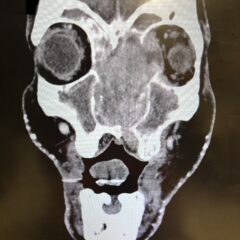

A Case Report of Corneoscleral Laceration with Open Globe Injury and Iris Prolapse

Open globe injury is defined as a full-thickness injury through all anatomical layers of the eye. Prolapse or herniation of the iris may be observed at presentation of an open globe injury, and iris prolapse is not well represented in the literature. This case report details the case of a 48-year-old male presenting with three hours of right eye pain after sustaining a traumatic injury due to a foreign body. Examination of the right eye revealed a 2 mm x 1 mm laceration to the 4-5 o’clock position with iris prolapse and plugging. The affected eye also revealed a teardrop-pupil with associated corectopia in the inferonasal direction and a 2 mm hyphema. The patient was diagnosed with a globe rupture and underwent same-day surgical intervention. This report emphasizes the use of fluorescein eye exams and explains the rationale against the measurement of intraocular pressures or removal of an obvious foreign body. The care provided represents strict adherence to the principles of management in ocular trauma and a positive outcome in which a patient’s vision and visual acuity were relatively maintained.